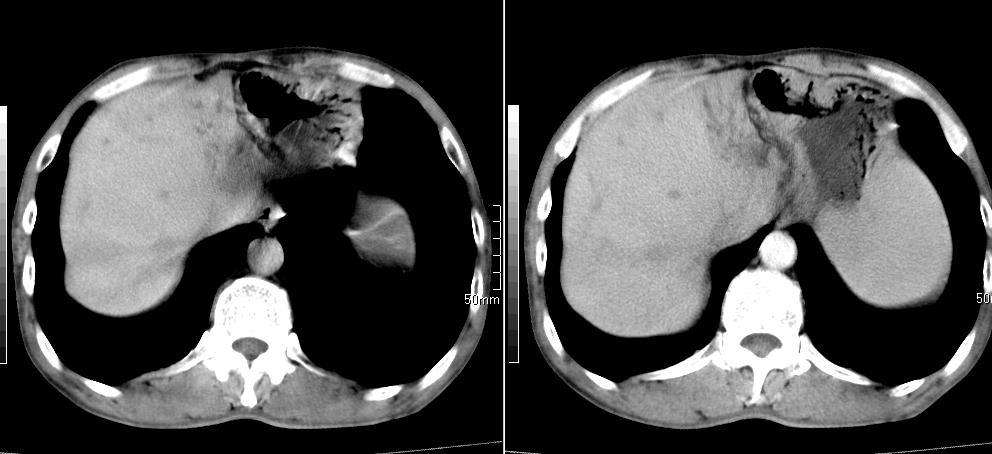

标题: CT26769:男,58岁,腹胀、腹部不适一年余 [打印本页]

标题: CT26769:男,58岁,腹胀、腹部不适一年余

1 慢性胰腺炎并假囊肿形成。2 慢性胆囊炎并累及肝边缘!

1)考虑慢性胰腺炎并假性囊肿形成。2) 慢性胆囊炎。3)肝内胆管扩张。

1肝内胆管扩张,性质待定,2慢性胰腺炎胰管扩张,胰腺颈部假囊肿,3肝左叶低密度为小囊肿,4胆囊炎。

1)考虑慢性胰腺炎并假性囊肿形成。2)肝内胆管稍扩张。